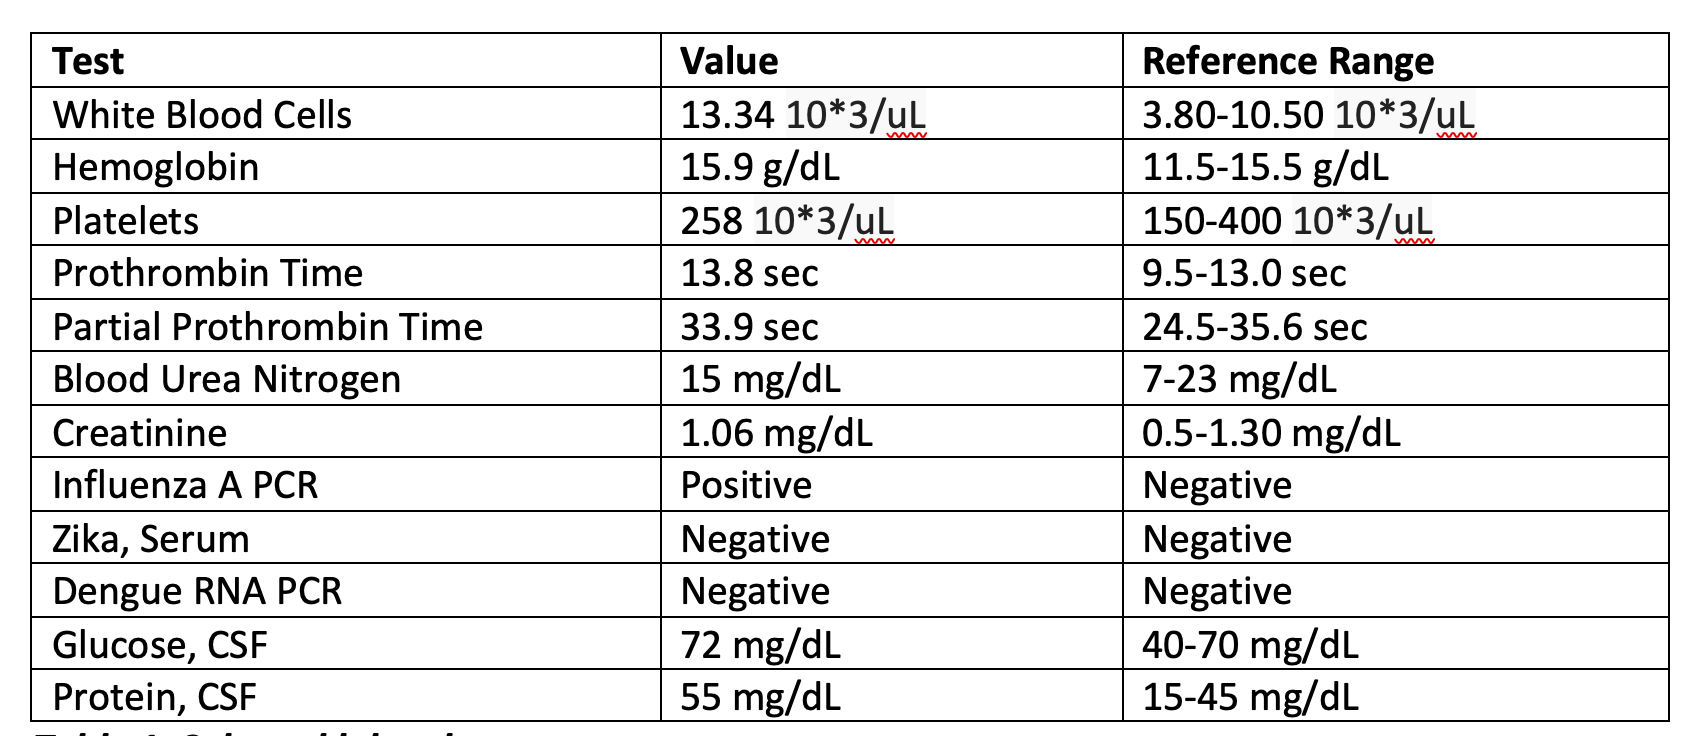

Case Presentation: A 43-year-old previously healthy male presented with acute onset mixed aphasia five days after recovering from an influenza A infection. He was last known well during a normal conversation with family before being found confused and unable to follow instructions at home. In the ED, initial CT and MRI brain imaging showed no acute ischemia, hemorrhage, midline shift, or herniation. Laboratory studies were notable for leukocytosis (WBC 13.34 × 10⁹/L), and urine drug screen was negative. On exam, he was alert and cooperative but exhibited severely impaired comprehension, repetition, naming, and reading, with preserved fluency. Lumbar puncture revealed an opening pressure with WBC 45 cells/µL (80% lymphocytes) and protein 68 mg/dL. CSF PCR was negative for HSV and VZV but positive for influenza A RNA, confirming the diagnosis of influenza-associated encephalitis. Additionally, his course was complicated by seizures in the right temporal lobe. He was treated with IV Peramivir, empiric acyclovir, and supportive care, then transitioned to oral Oseltamivir for a 10-day course. His symptoms resolved completely within five days, and follow-up MRI two weeks later showed near-complete resolution of temporal lobe lesions.

Discussion: IAE is a rare but serious complication of influenza infection, with most cases reported in pediatric populations. In adults, the condition is often underdiagnosed due to its nonspecific presentation. Pathogenesis involves both direct viral neuroinvasion and immune-mediated injury, leading to cerebral edema and encephalopathy. Diagnosis requires a high index of suspicion, especially in influenza season, and should include nasopharyngeal and CSF PCR testing, along with neuroimaging to differentiate IAE from other viral encephalitides such as HSV. Our case demonstrated classic findings, including bilateral temporal lobe hyperintensities on MRI and influenza A detection in CSF.Management strategies are largely supportive but should include early initiation of neuraminidase inhibitors, empiric antiviral coverage for alternative causes until ruled out, and intensive monitoring for complications such as seizures or cerebral edema. Prognosis is variable, with reported adult mortality rates between 10% and 30%. Our patient’s complete neurological recovery underscores the benefit of timely diagnosis and prompt antiviral therapy.

Conclusions: This case of influenza A is very rare in presenting with both a seizure and encephalitis. Influenza-associated encephalitis is a rare but potentially life-threatening complication of influenza in adults. Clinicians should consider IAE in any patient presenting with acute encephalopathy during influenza season. Early neuroimaging, CSF analysis, and molecular diagnostics are essential for accurate diagnosis. Prompt antiviral therapy and supportive care can significantly improve patient outcomes, as demonstrated in this case.